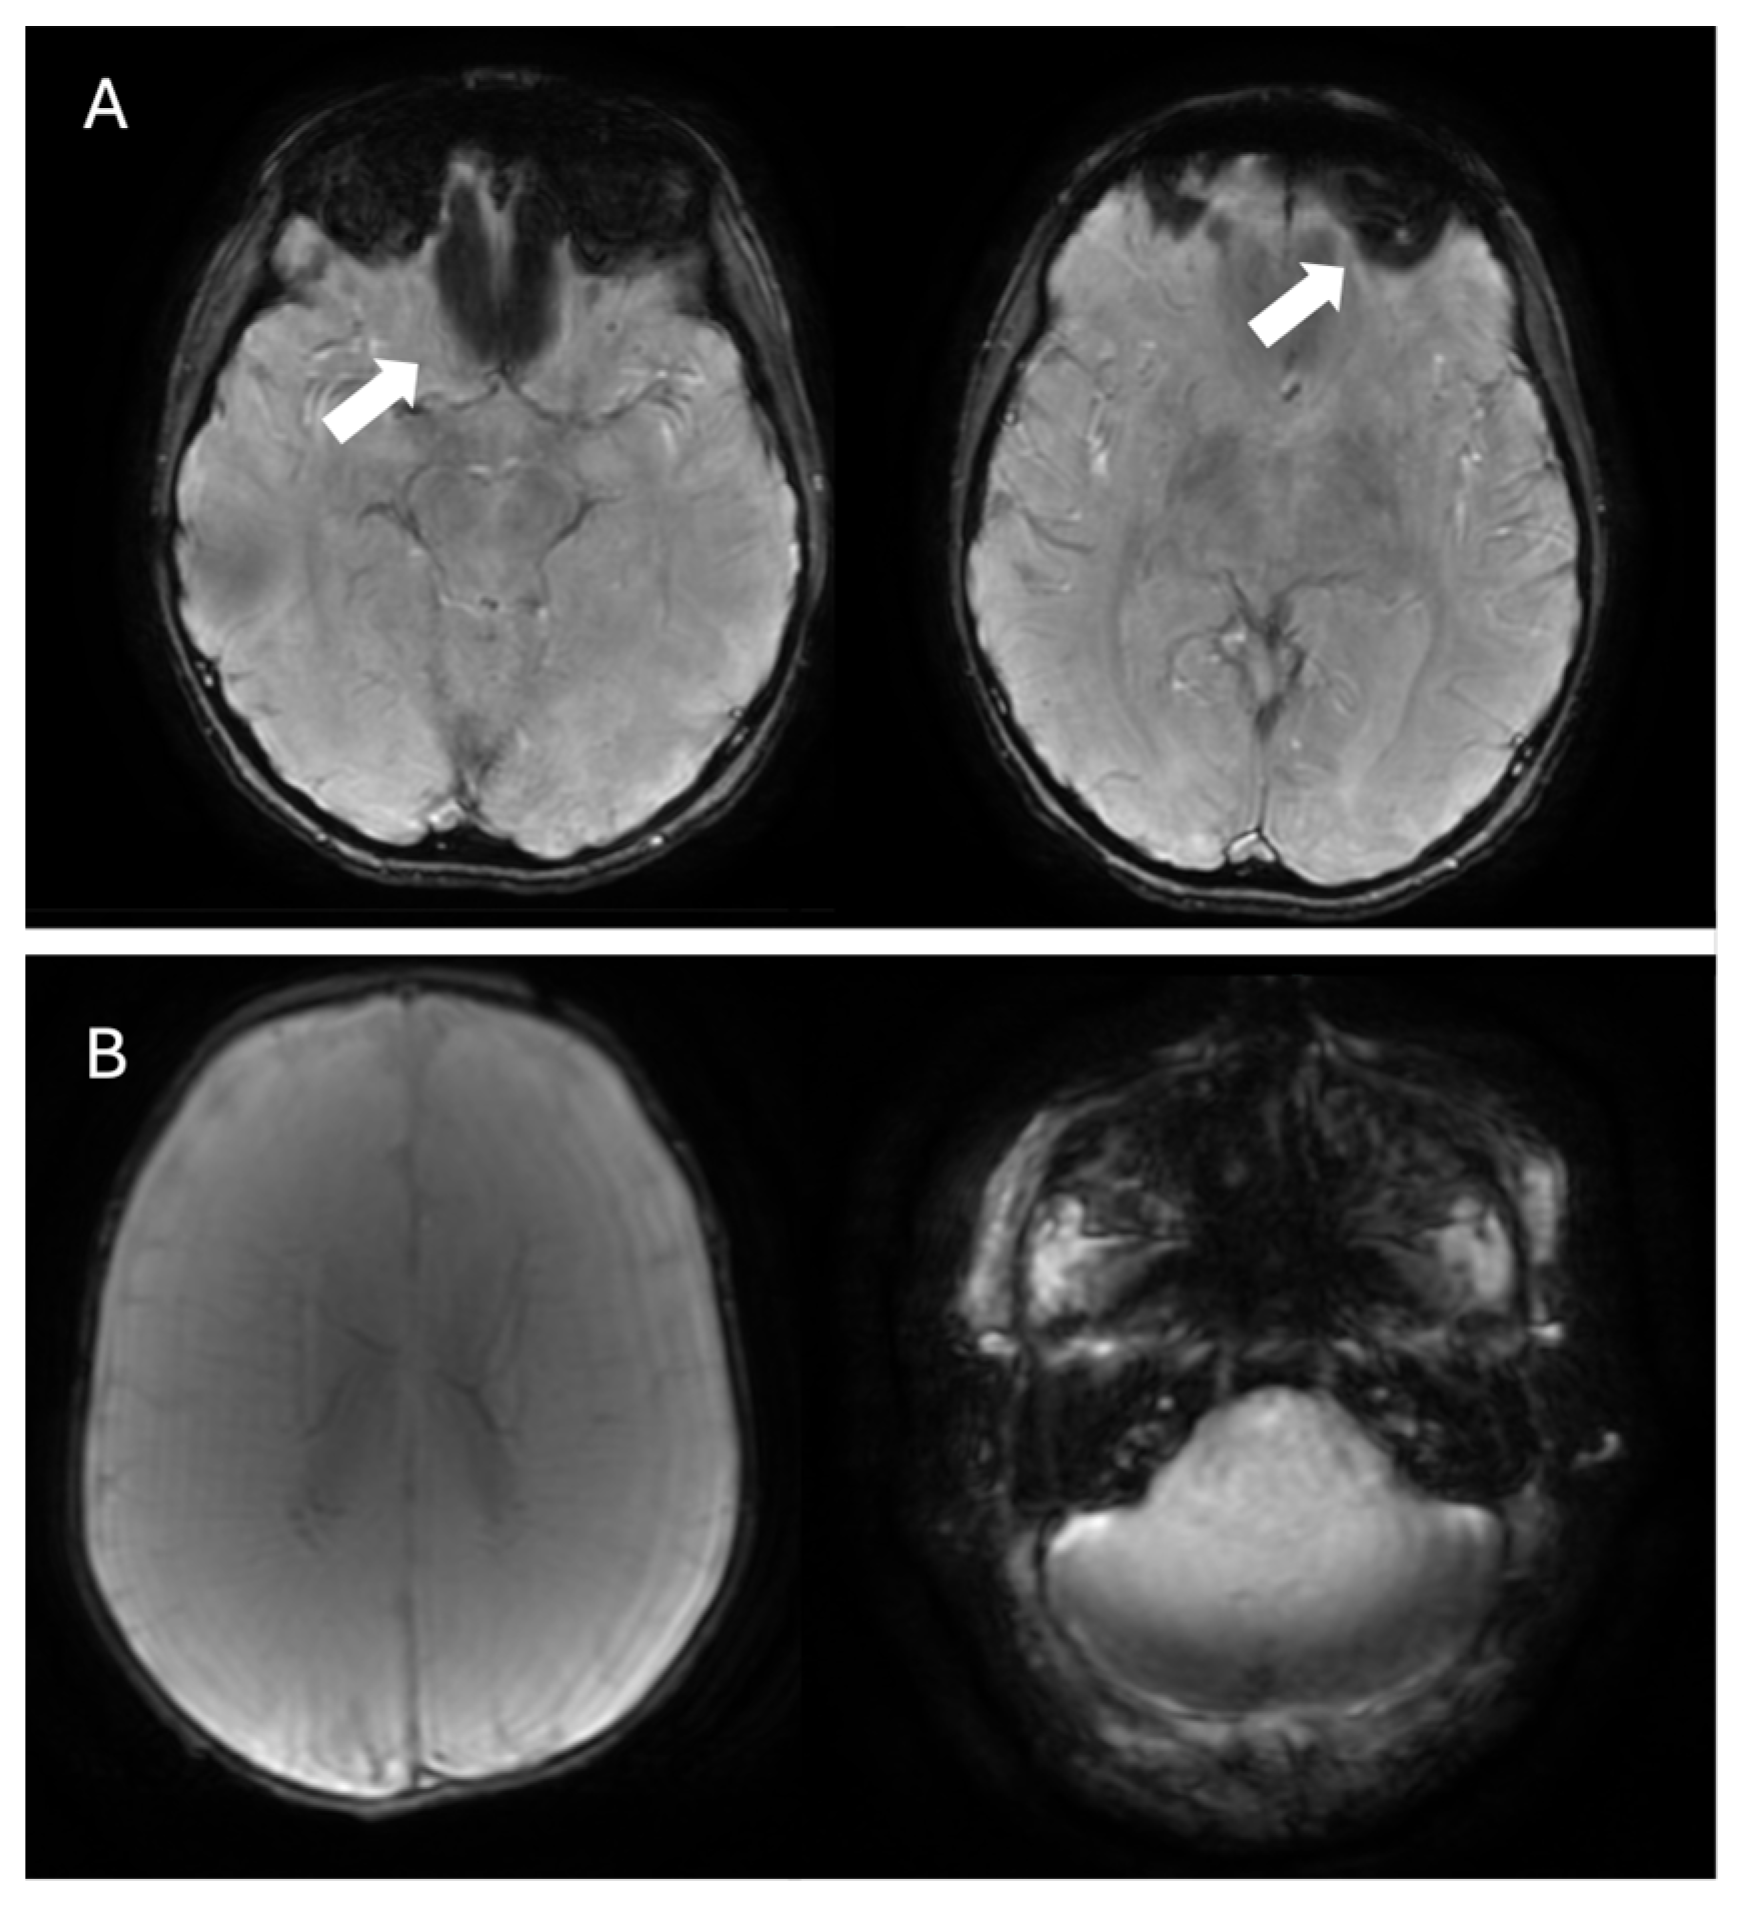

- Mesker, D.J.; Poels, M.M.F.; Ikram, M.A.; Vernooij, M.W.; Hofman, A.; Vrooman, H.A.; van der Lugt, A.; Breteler, M.M.B. Lobar Distribution of Cerebral Microbleeds. Arch. Neurol. 2011, 68, 656–659. [Google Scholar] [CrossRef] [PubMed]

- Rubin, A.; Waszczuk, Ł.; Trybek, G.; Kapetanakis, S.; Bladowska, J. Application of susceptibility weighted imaging (SWI) in diagnostic imaging of brain pathologies—A practical approach. Clin. Neurol. Neurosurg. 2022, 221, 107368. [Google Scholar] [CrossRef]

- Sharma, R.; Dearaugo, S.; Infeld, B.; O’Sullivan, R.; Gerraty, R.P. Cerebral amyloid angiopathy: Review of clinico-radiological features and mimics. J. Med. Imaging Radiat. Oncol. 2018, 62, 451–463. [Google Scholar] [CrossRef] [PubMed]

- Linn, J.; Halpin, A.; Demaerel, P.; Ruhland, J.; Giese, A.; Dichgans, M.; van Buchem, M.; Bruckmann, H.; Greenberg, S. Prevalence of superficial siderosis in patients with cerebral amyloid angiopathy. Neurology 2010, 74, 1346–1350. [Google Scholar] [CrossRef] [PubMed]

- Lopes, P.A.; Raposo, N.; Charidimou, A.; Zotin, M.Z.; Gurol, M.E.; Greenberg, S.; Viswanathan, A. SWI versus GRE-T2*: Assessing cortical superficial siderosis in advanced cerebral amyloid angiopathy. Rev. Neurol. 2024, 180, 532–538. [Google Scholar] [CrossRef]

- Charidimou, A.; Boulouis, G.; Frosch, M.P.; Baron, J.-C.; Pasi, M.; Albucher, J.F.; Banerjee, G.; Barbato, C.; Bonneville, F.; Brandner, S.; et al. The Boston criteria version 2.0 for cerebral amyloid angiopathy: A multicentre, retrospective, MRI–neuropathology diagnostic accuracy study. Lancet Neurol. 2022, 21, 714–725. [Google Scholar] [CrossRef]